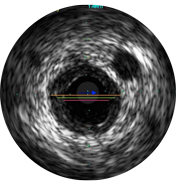

Диаметры сосудов можно определять в проксимальных и дистальных контрольных точках за счет значений диаметров просветов, средних диаметров стенок (в центральной точке между просветом и сосудом) или диаметров сосудов.

ВСУЗИ помогает более точно определить степень и тип стеноза (т.е. минимальную площадь просвета (MLA), объем бляшки и кальций). Несмотря на то что ВСУЗИ позволяет выявить разрыв бляшки, наличие тромбов и диссекции, кальций наиболее распространен при рутинных ЧКВ. Оказывая большее влияние на стратегию стентирования, кальций отображается в виде очень ярких участков с акустическим затенением, которое блокирует изображение сзади. Также могут наблюдаться реверберации.